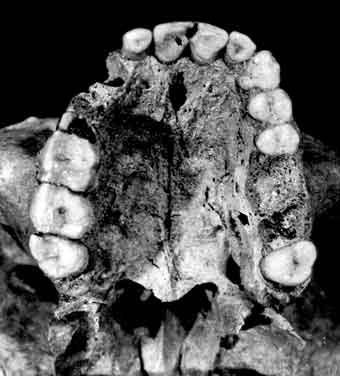

Cáries, desgastes, cálculos, perda dos dentes em vida e abcessos estão estreitamente relacionados com o tipo de alimento utilizado no cotidiano destes grupos. Mudanças no modo de vida, como a transição do sistema de caça e coleta para a agricultura, quando os alimentos ingeridos, além de mais ricos em carboidratos, passaram a ser melhor processados, associam-se à variações importantes na ocorrência de patologias dentárias e maxilares.

Aumento na prevalência de cáries, e desgastes menos intensos, são geralmente encontrados em grupos agricultores, e tornam-se mais graves com o consumo de alimentos industrializados e com muito açúcar. Nos Esquimó, por exemplo, a saúde dos dentes piorou depois do contato com os Europeus.

Infecções e deficiências de nutrição aparecem como defeitos na formação do esmalte dentário. O uso de adornos labiais, chamados tembetás, e o uso dos dentes como instrumentos, para arrancar ou cortar objetos, também podem ser estudados a partir de desgastes dos dentes e da perda dentária em vida. O hábito de palitar os dentes chega a formar sulcos visíveis. A má higiene da boca, associada a certos tipos de alimentos que propiciam o tártaro, ou cálculo dental, causando inflamação das gengivas e deixando marcas nos ossos.